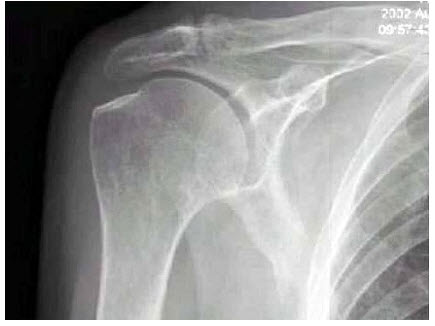

8、单项选择题

右肩关节活动受限1年多,体检发现右手上抬不能,后展受限,行右肩关节摄片如图示,最可能的诊断是()

A.正常右肩关节

B.右肱骨骨质疏松

C.右肩关节周围炎

D.右肩关节滑囊炎

E.右肩关节结核